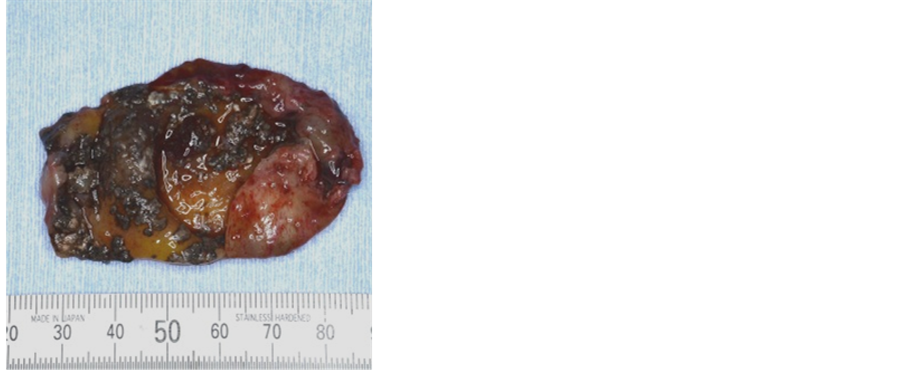

Root canal therapy followed by surgical enucleation of the cystic lesion and apicoectomy with 24, 25, 26 was carried out under general anesthesia. An intraoral approach was used, and the lesion was exposed and could be easily removed from the bone without adhesion (Figure 4). The excised tumor measured 40 × 45 mm, had a smooth surface, and was elastic soft to palpation. Sectional view showed a unicystic lesion containing calcifications in the cystic wall (Figure 5).

Figure 5. Sectional view showed a unicystic lesion containing calcifications.